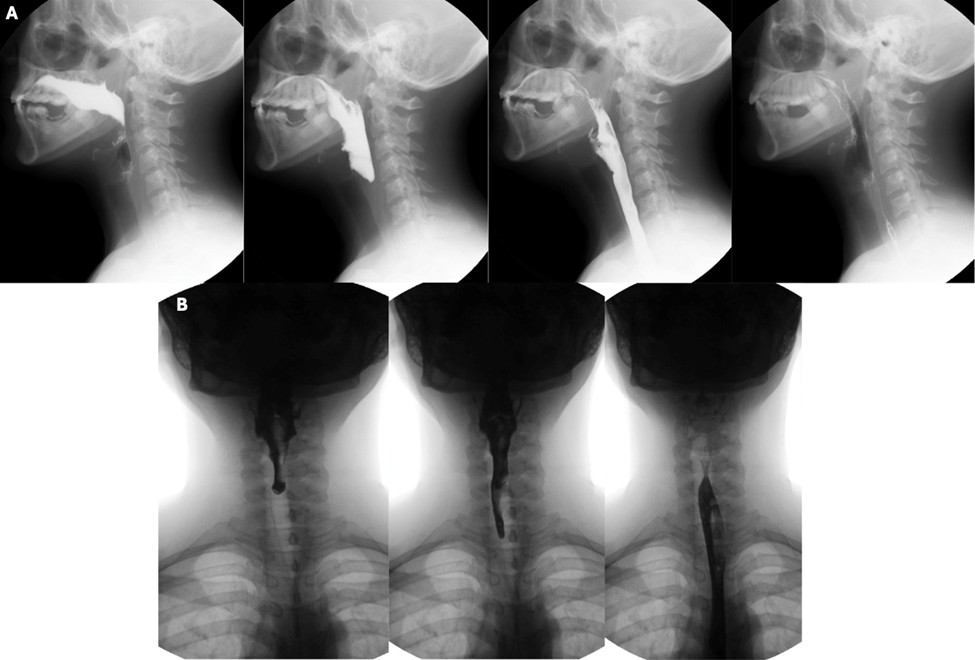

Figure 10: Spectrum of airway protection impairment severity - penetration (A), aspiration (B) and aspiration that reaches the right main bronchus (C)

Penetration and aspiration can be classified according to the timing of their occurrence, which helps to identify the underlying causal mechanism. When there is incomplete closure of the larynx or delayed triggering of the swallow reflex, contrast enters the airway during the pharyngeal phase of deglutition. Aspiration can also occur before the pharyngeal phase of deglutition, typically in the setting of posterior escape from the oral cavity or poor coordination in oropharyngeal bolus transport. On the other hand, aspiration can also occur after the pharyngeal phase of deglutition when there are persistent pharyngeal residues that can spill into the airway when the larynx opens - this occurs when pharyngeal clearance is hindered by insufficient contraction of pharyngeal muscles, incomplete opening of the upper oesophageal sphincter or presence of obstructive masses. (Fig. 11)

Figure 11: Range of underlying causes for compromised airway protection. (A) Posterior bolus escape from the oral cavity resulting in laryngeal penetration before the pharyngeal phase of deglutition; (B) Aspiration of contrast during the pharyngeal phase of deglutition due to delayed triggering of the swallow reflex; (C) Persistent pharyngeal residues that resulted in the aspiration seen in the panel B of figure 10